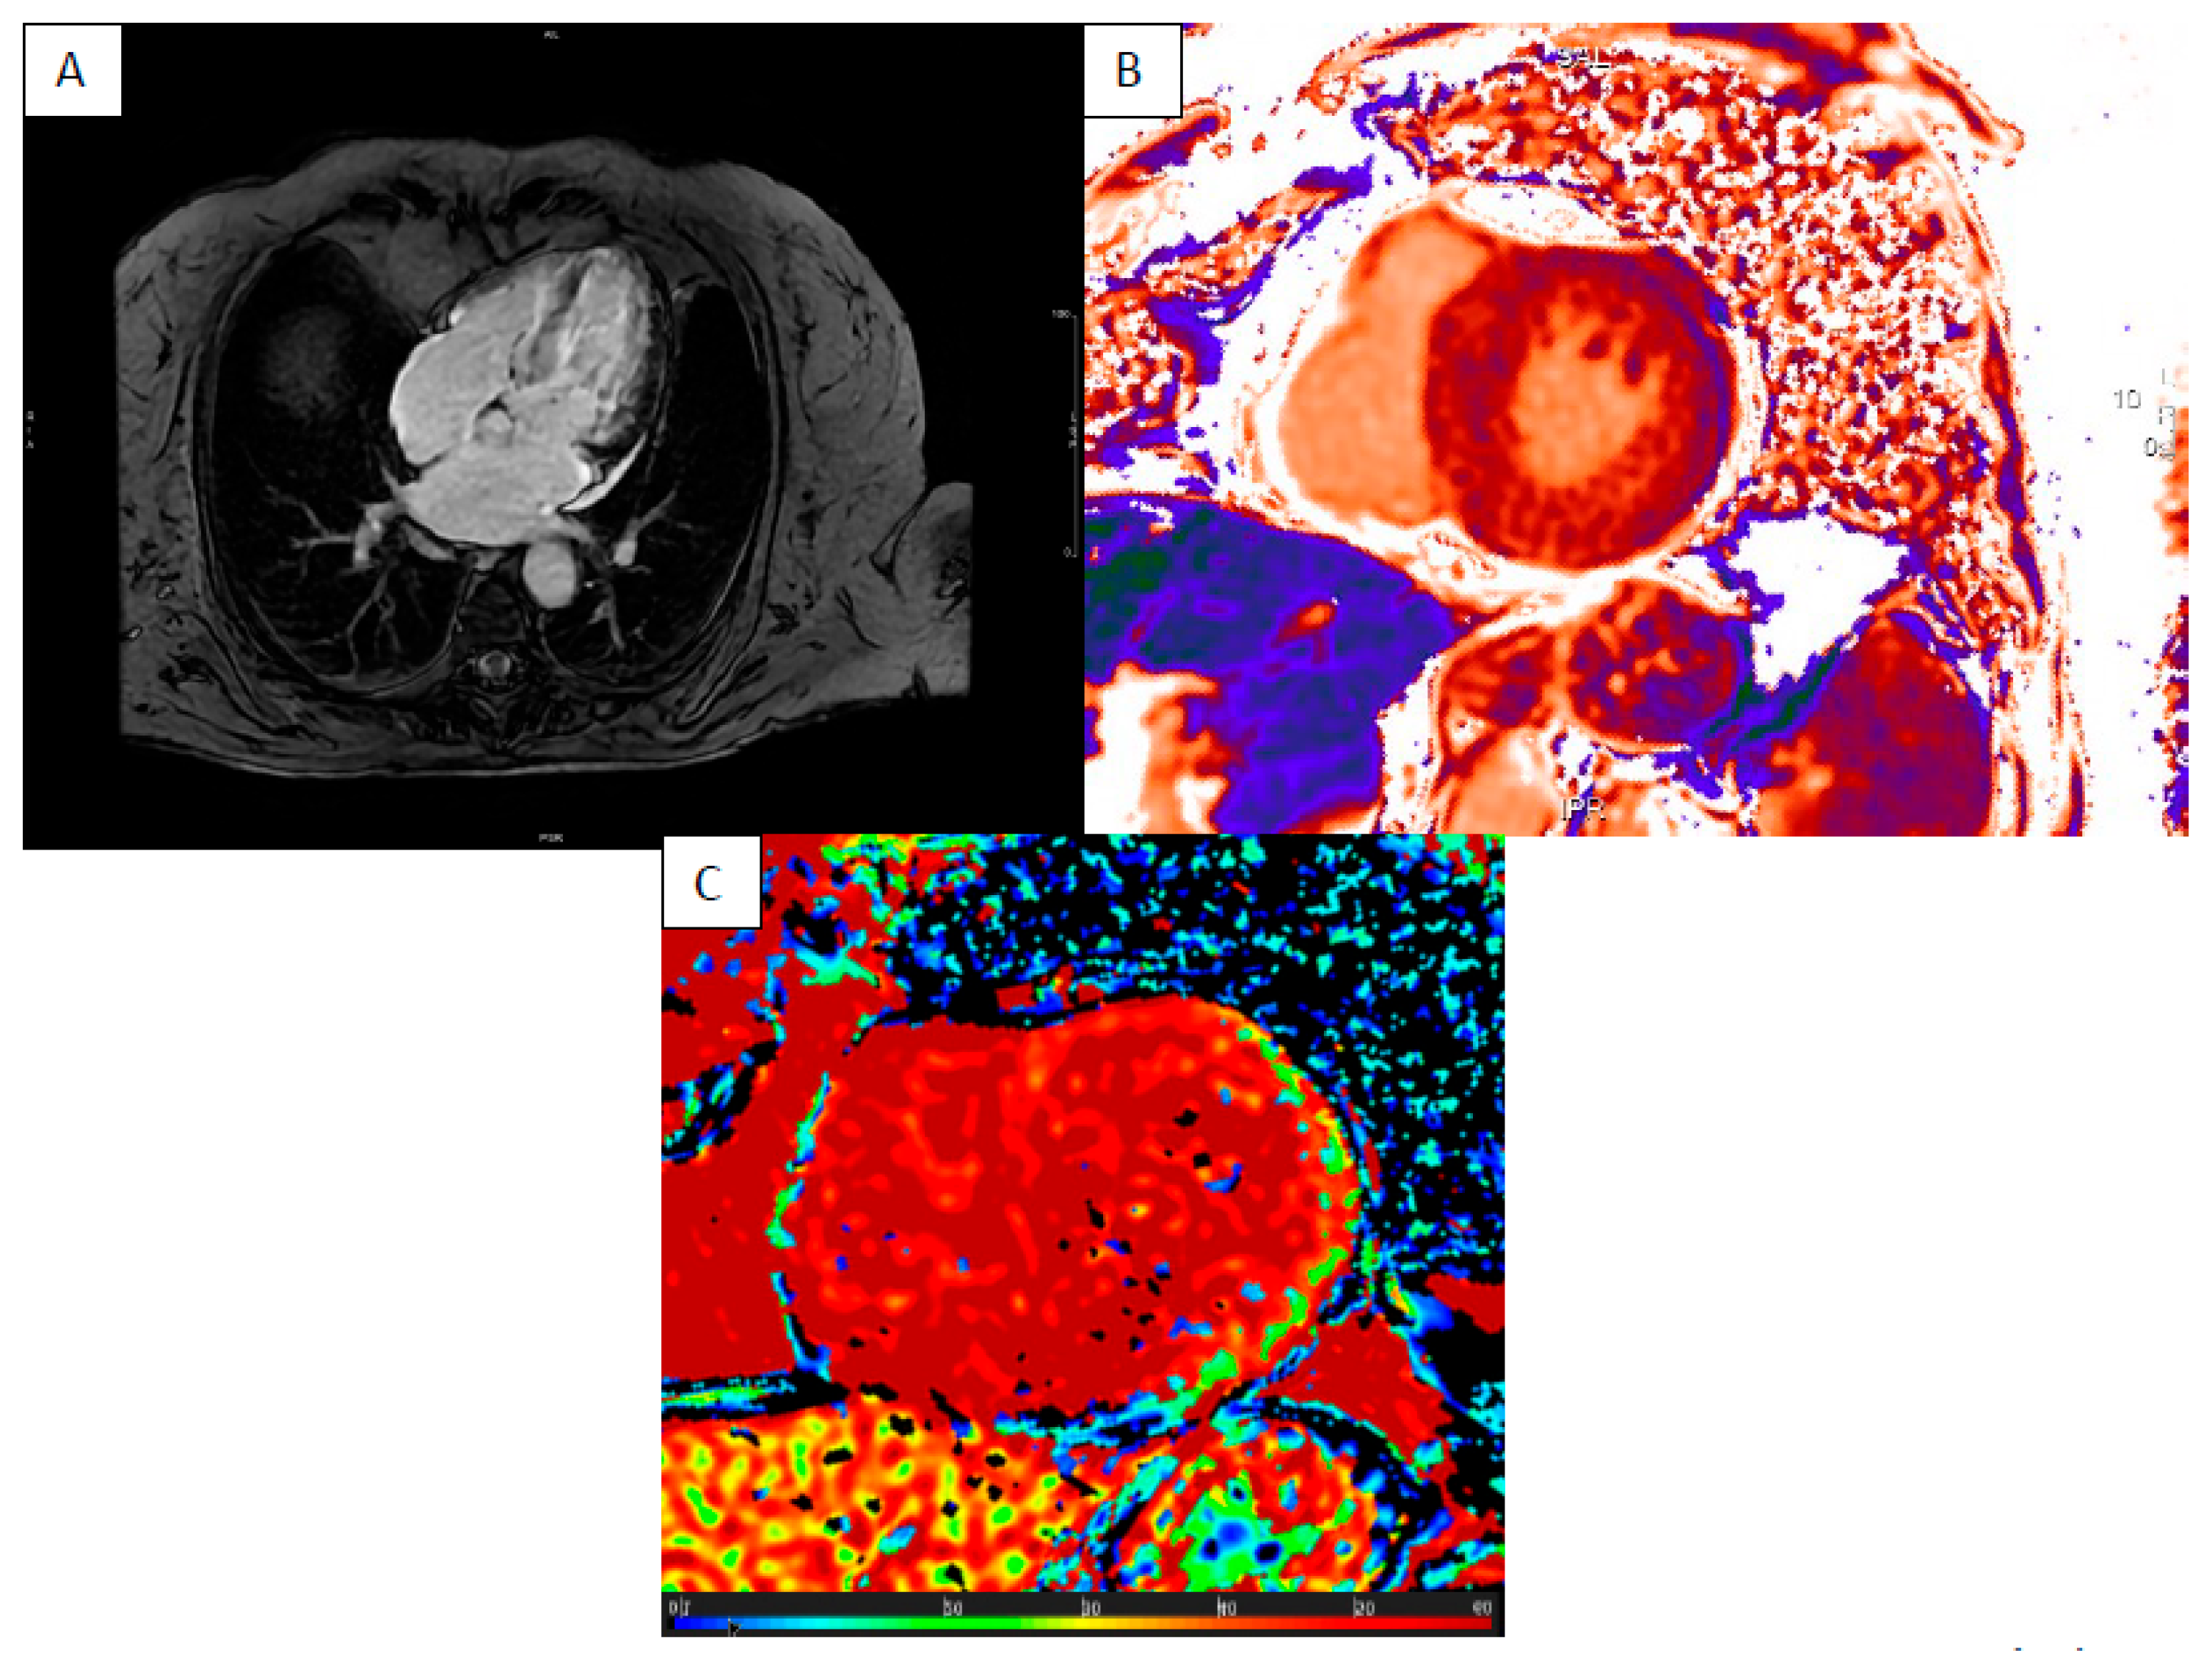

6. Myocardial Iron Overload